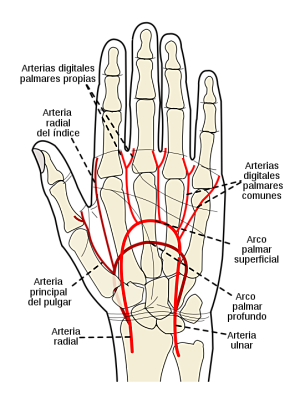

El suministro vascular del flexor corto del pulgar está asegurado por la arteria radial, terminaciones superficiales y algunas ramas que emite desde el arco palmar superficial, que es una compleja red vascular que forman la arteria radial y la cubital.